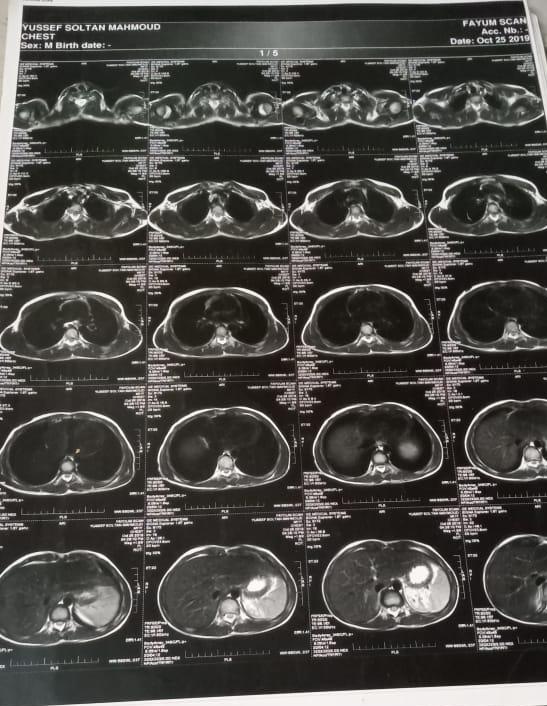

واستكملت: «أظهرت الأشعة أنه يعاني من نزيف في 3 فقرات بالعمود الفقري، م=ما أدى إلى إصابته بضمور العضلي الشوكي، وأُجريت له عملية جراحية لتفريغ العمود الفقري من الدم».